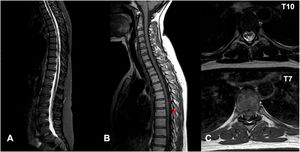

Nervous system involvement is uncommon in granulomatosis with polyangiitis (GPA), a systemic autoimmune disease with episodes of necrotizing vasculitis. It is usually due to the compressive effect of dural or epidural masses. Spinal hemorrhagic presentation is exceptional. A 41-year-old woman diagnosed with GPA presented with three episodes of acute spinal subdural hematoma separated by eight years and ten months, respectively. The symptomatic debut was pain and paresis in all episodes. On all occasions, a lesion compatible with acute spinal subdural hematoma was diagnosed by magnetic resonance imaging (MRI). All episodes were treated conservatively with corticosteroids and immunosuppressants. The patient presented complete neurological recovery in the first two episodes. A mild residual left lower limb paresis remains after the last one. Follow-up MRI was performed after all episodes, and no focal intraspinal lesions were detected. Spinal subdural hemorrhage is a form of manifestation of GPA, either as a debut or in the course of the disease. We describe the third confirmed case of spontaneous spinal hemorrhage secondary to GPA published in the literature and the first with recurrence. Given the extraordinary response to immunosuppressive therapy, a high level of clinical suspicion is necessary to establish treatment as early as possible.

Presentamos un caso en una paciente diagnosticada de granulomatosis con poliangeitis (GPA) que presentó en dos ocasiones separadas por un lapso de 8 años, hematoma subdural agudo espinal con diferentes niveles de afectación en cada uno de los episodios. Se añade una revisión de la literatura. Una mujer de 48 años diagnosticada de GPA, presentó tres episodios de hematoma subdural espinal agudo; separados por un período de tiempo en primer lugar de 8 años y en segundo lugar de 10 meses. Clínicamente, las tres veces se manifestaron con dolor y paresia. En todas las ocasiones, se diagnosticó mediante Resonancia Magnética Nuclear (RMN) la presencia de una lesión compatible con hematoma subdural espinal agudo. Todos los episodios se trataron de forma conservadora con corticoesteroides y Rituximab. La paciente presentó recuperación neurológica completa en los dos primeros episodios. En relación al último; presenta una paresia leve en miembro inferior izquierdo. En todos los episodios se realizó control por RMN y no se detectaron alteraciones intraespinales. La hemorragia subdural espinal es una posible forma de manifestación de la GPA, bien como debut o en el curso de la enfermedad. Es necesario un alto nivel de sospecha clínica para establecer el tratamiento de la forma más precoz posible. Presenta una respuesta extraordinaria a la terapia inmunosupresora. Es posible una recuperación completa a través del tratamiento conservador. Recomendamos un abordaje combinado.